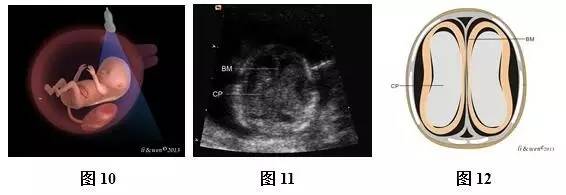

(一)11~13+6孕周正常胎儿颅脑及颜面方法及内容

超声扫查方法:声束平面从胎儿前额进入,通过胎儿侧脑室对胎儿颅脑进行横切面扫查(图10),即可获得侧脑室水平横切面(图11,12);然后声束平面以前额为基点,向胎儿尾侧和前方扫查(图13,16,19,22),依次可获得小脑水平横切面(图14,15)、双眼球冠状切面(图17,18)、鼻后三角冠状切面(图20,21)和鼻唇冠状切面(图23,24)。

标准切面判断标准:(1)侧脑室水平横切面:可观察到强回声的脑中线把两侧大脑半球分开,两侧大脑半球内主要为侧脑室及其内的脉络丛占据,大脑实质仅表现为侧脑室周围薄层低回声带,强回声脉络丛几乎充满两侧侧脑室。(2)小脑横切面:可观察到脑中线、丘脑、小脑、第四脑室及颅后窝池等。(3)双眼球冠状切面:可观察到双眼球、硬腭、下颌骨、双耳等。(4)鼻后三角冠状切面:可观察到两块鼻骨、上颌骨、上牙槽及下颌骨等结构。(5)鼻唇冠状切面:可观察到上唇、下唇及鼻等结构。

注:BM为脑中线;CP为脉络丛;T为丘脑;CB为小脑;CM为颅后窝池;EYES为眼球;EAR为耳;NB为鼻骨;SM为上颌骨;IM为下颌骨;ST为上牙槽;N为鼻;UL为上唇;LL为下唇;CH,小脑半球;CV,小脑蚓部;CP,脉络丛;FV,第4脑室;B,脑干

图10~24胎儿颅脑及颜面扫查方法及超声声像图和模式图。图10侧脑室横切面扫查模式图;图11、12侧脑室横切面声像图及模式图;图13小脑横切面扫查模式图;图14、15小脑横切面声像图及模式图;图16双眼球冠状切面扫查模式图;图17、18双眼球冠状切面声像图及模式图;图19鼻后三角冠状切面扫查模式图;图20、21鼻后三角冠状切面声像图及模式图;图22鼻唇冠状切面扫查模式图;图23、24鼻唇冠状切面声像图

主要观察的解剖结构及内容:侧脑室横切面主要观察脑中线是否存在,左右大脑半球是否对称等。小脑横切面主要观察脑中线是否存在,颅后窝池是否存在等。双眼球冠状切面主要观察双侧眼球是否存在、大小及位置,双耳是否存在,硬腭是否连续完整等。鼻后三角冠状切面主要观察鼻骨是否存在,上牙槽是否连续完整等。鼻唇冠状切面主要观察上唇是否连续完整、鼻的形态等。